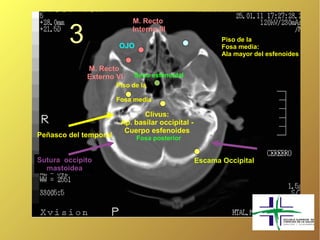

M. Recto

3               OJO

Interno III

Piso de la

Fosa media:

Ala mayor del esfenoides

Externo VI      Seno esfenoidal

Fosa media

Clivus:

Ap. basilar occipital -

Cuerpo esfenoides

Peñasco del temporal          Fosa posterior

Sutura occipito                                   Escama Occipital

mastoidea

M. Recto 3 OJO Interno III Piso de la Fosa media: Ala mayor del esfenoides M. Recto Externo VI Seno esfenoidal Piso de la Fosa media Clivus: Ap. basilar occipital - Cuerpo esfenoides Peñasco del temporal Fosa posterior Sutura occipito Escama Occipital mastoidea